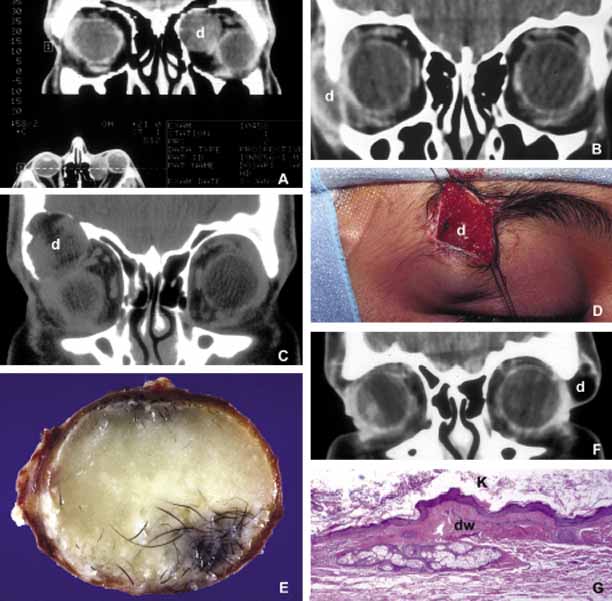

Choristoma, however, is a tumor-like proliferation of tissues that are not normally present at a given body location. The most commonly encountered example of orbital choristoma is a dermoid.16 Dermoids that present with many varieties result from the entrapment of epithelial structures at the site of closure of fetal fissures. Superficial dermoid cysts occur primarily subcutaneously anterior to orbital septum or within the anterior orbit. If the cyst wall is made of epidermis without dermal tissues, it is classified as an epidermoid cyst. These lesions are occasionally lined by conjunctival or pseudostratified respiratory epithelium.17 The superficial lesions must be distinguished from deep orbital dermoids that are usually rounded, encapsulated tumors filled with fatty materials, keratin, and dermal structures such as hair particles. Histopathologically the dermoid wall is lined by keratizing squamous epithelium with dermal appendices including hair follicles and sebaceous and eccrine glands.18

Most of the dermoids are well outlined by ultrasonography because of their anterior location thus making CT or MRI rarely necessary.19 If the dermoid is unusually large or located at the frontal zygomatic suture, CT is necessary to document the relationship of the lesion to the bone before surgical intervention. Rarely, dermoids at the fronto-zygomatic suture may develop dumbbell-shaped lesions partially within the orbit and partially extending into the temporal fossa.20,21 Unusually large superior orbital dermoids particularly those that leak and create granulomatous reaction within adjacent soft tissues may erode the bone and extend into the frontal sinus or the cranium (Fig. 2).

Fig. 2 Dermoid. Different presentations of dermoid (d): superior medial, semi-solid mass pushing the globe down and out (A); a ruptured dermoid causing an inflammatory reaction within adjacent soft tissues (B); a large superior lateral dermoid eroding through the roof of the orbit to extend into the brain (C); extraorbital dermoid within the subcutaneous tissues of the eyebrow (D); gross appearance of the cystic dermoid containing whitish yellow cheesy keratin material intermixed with hair (E); dumbbell dermoid that is present on both sides of the frontozygomatic fissure (F); histopathology of dermoid wall (dw) containing skin appendages, the lumen of the dermoid is lined with stratified squamous epithelium producing keratin (K) (G). ([E] is the courtesy of Amin M. Nasr, MD of Beirut, Lebanon)